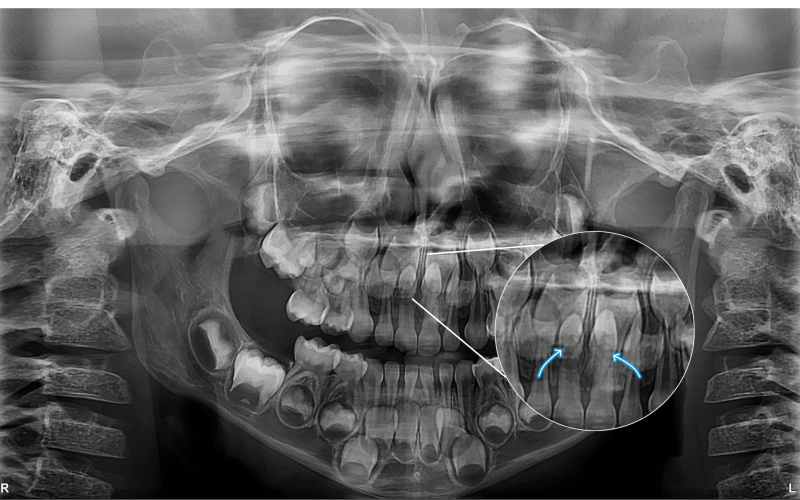

Na imagem panorâmica apresentada, observam-se dois dentes supranumerários localizados na região anterior da maxila, sobrepostos aos germes dos dentes 11 e 21 (incisivos centrais superiores).

• Localizar exatamente os dentes supranumerários;

• Avaliar sua relação com os germes permanentes;

• Evitar complicações cirúrgicas e garantir a preservação das estruturas anatômicas vizinhas.